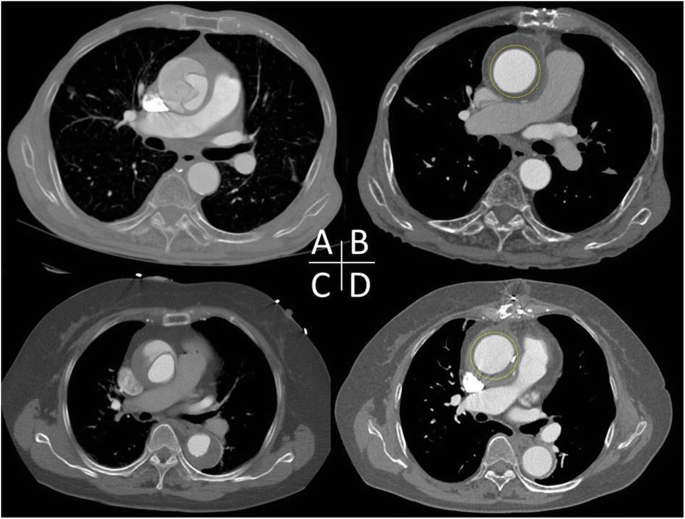

Median sternotomy was made and cardiopulmonary bypass was implemented through femoral arterial cannulation and single two-stage venous cannulation via right atrial appendage. The ascending aorta was carefully separated from the pulmonary artery trunk and the right pulmonary artery. Most care was taken during the dissection to avoid tearing the false lumen of the dissected aorta. Pieces of artificial graft was tailored, placed around the aorta from the coronary ostia up to the innominate artery in a stepwise fashion, and approximated with a running suture of 4–0 Prolene (Ethicon, Somerville, NJ) to tightly wrap the dissected ascending aorta (Fig. 1). We used Triplex graft® (Vascutek Terumo, Tokyo, Japan) as an artificial graft, which has the remarkable characteristics of excellent impermeability without biologic material coating [3]. The reason why we use separate piece of graft is for the snug fitting against the curved nature of the ascending aorta and size discrepancy between the proximal and distal ascending aorta, which can lead to prevent graft migration. We calculated the size of the graft so that the diameter of the wrapped aorta would measure around 40 mm to the dimensions of the patient and the preoperative CT scan. The aim was to significantly reduce the diameter of the aorta and maximize opposition between the false and true lumen. The overall operation times and cardiopulmonary bypass times were 91 and 31 min (Patient 1), and 80 and 23 min (Patient 2), respectively. There was no operative death. The postoperative hospital stays (10 and 8 days) were uneventful. At follow-up (38 and 30 months), the patients were doing well and were self-catering. Follow-up operative computed tomographic scans demonstrated a single lumen with the reapplication of the false lumen in the wrapped ascending aorta, and the absence of dissection or aneurysmal change in the entire aorta, in both patients (Fig. 2).